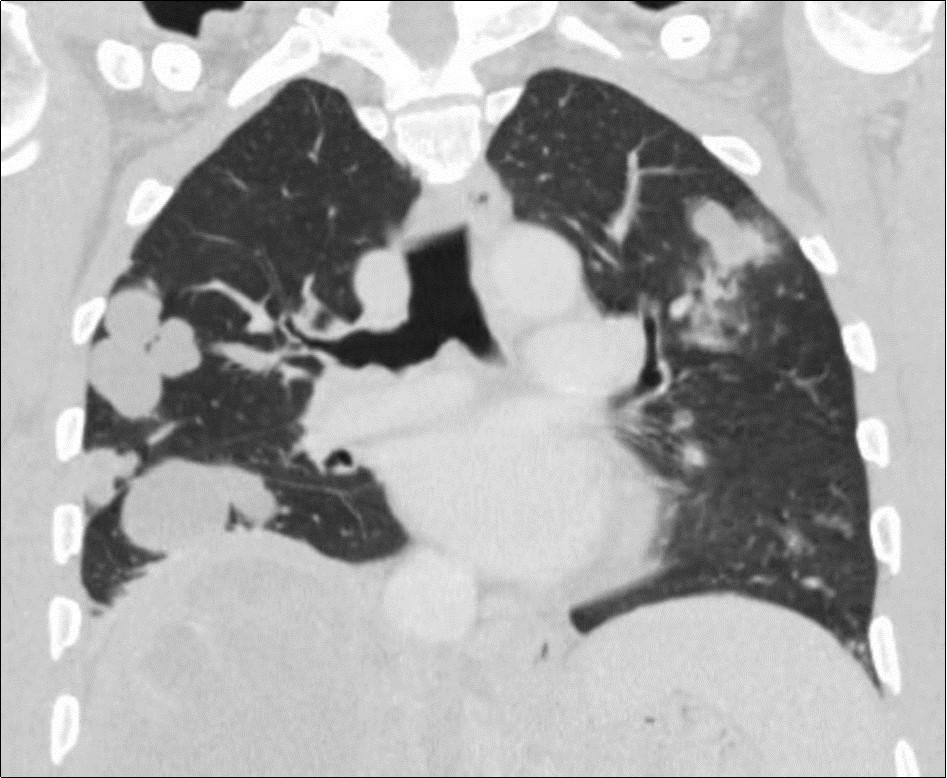

A 50-year-old man, was referred to our center for abdominal pain that had persisted for 1 month with marked loss of weight. An abdominal ultrasound completed by CT scan revealed a tumor of 15 centimeters of main axis of the right liver associated in contact with the portal vein associated with bilateral pulmonary nodules (Figure 1, Figure 2). Family and personal history for tuberculosis were negative. On admission, there was no fever, the abdomen was soft and non-tender, and there was a painful hepatomegaly without palpable mass. Blood showed anicteric cholestasis. Hydatid serology as well as tuberculin skin tests were negative. Upper and lower digestive endoscopy as well as tumor markers were normal. An ultrasound-guided fine-needle biopsy showednecro-inflammatory changes of the liver parenchyma without any signs of malignancy or specificity. Concerning the pulmonary lesions, there were no proof of active tuberculosis (sputum examination and bronchoalveolar lavage showed no BK). Patient received empiric antibiotherapy (amoxicillin and clavulanic acid) with regression of the pulmonary lesions in the control X Ray.

Figure 2.Coronal CT scan showing multiple bilateral pulmonary masses of both lungs associated with centrilobularmicronodules